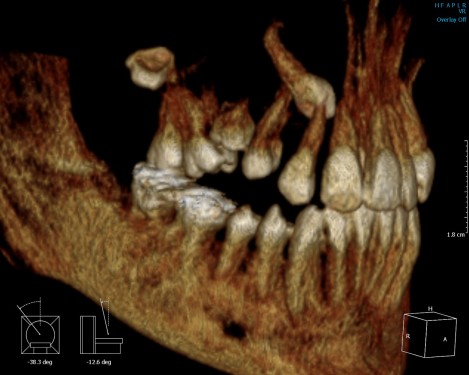

Arrested-eruption-of-first-permanent-molar

Arrested eruption of first permanent molar – frequency, clinical problems and analysis

Пробива на зъбите е естествен процес, при който формираният зъбен зародиш се доразвива и придвижва към своята позиция в челюстта до функционалното му положение в устната кухина и влизане в контакт с неговия антагонист.